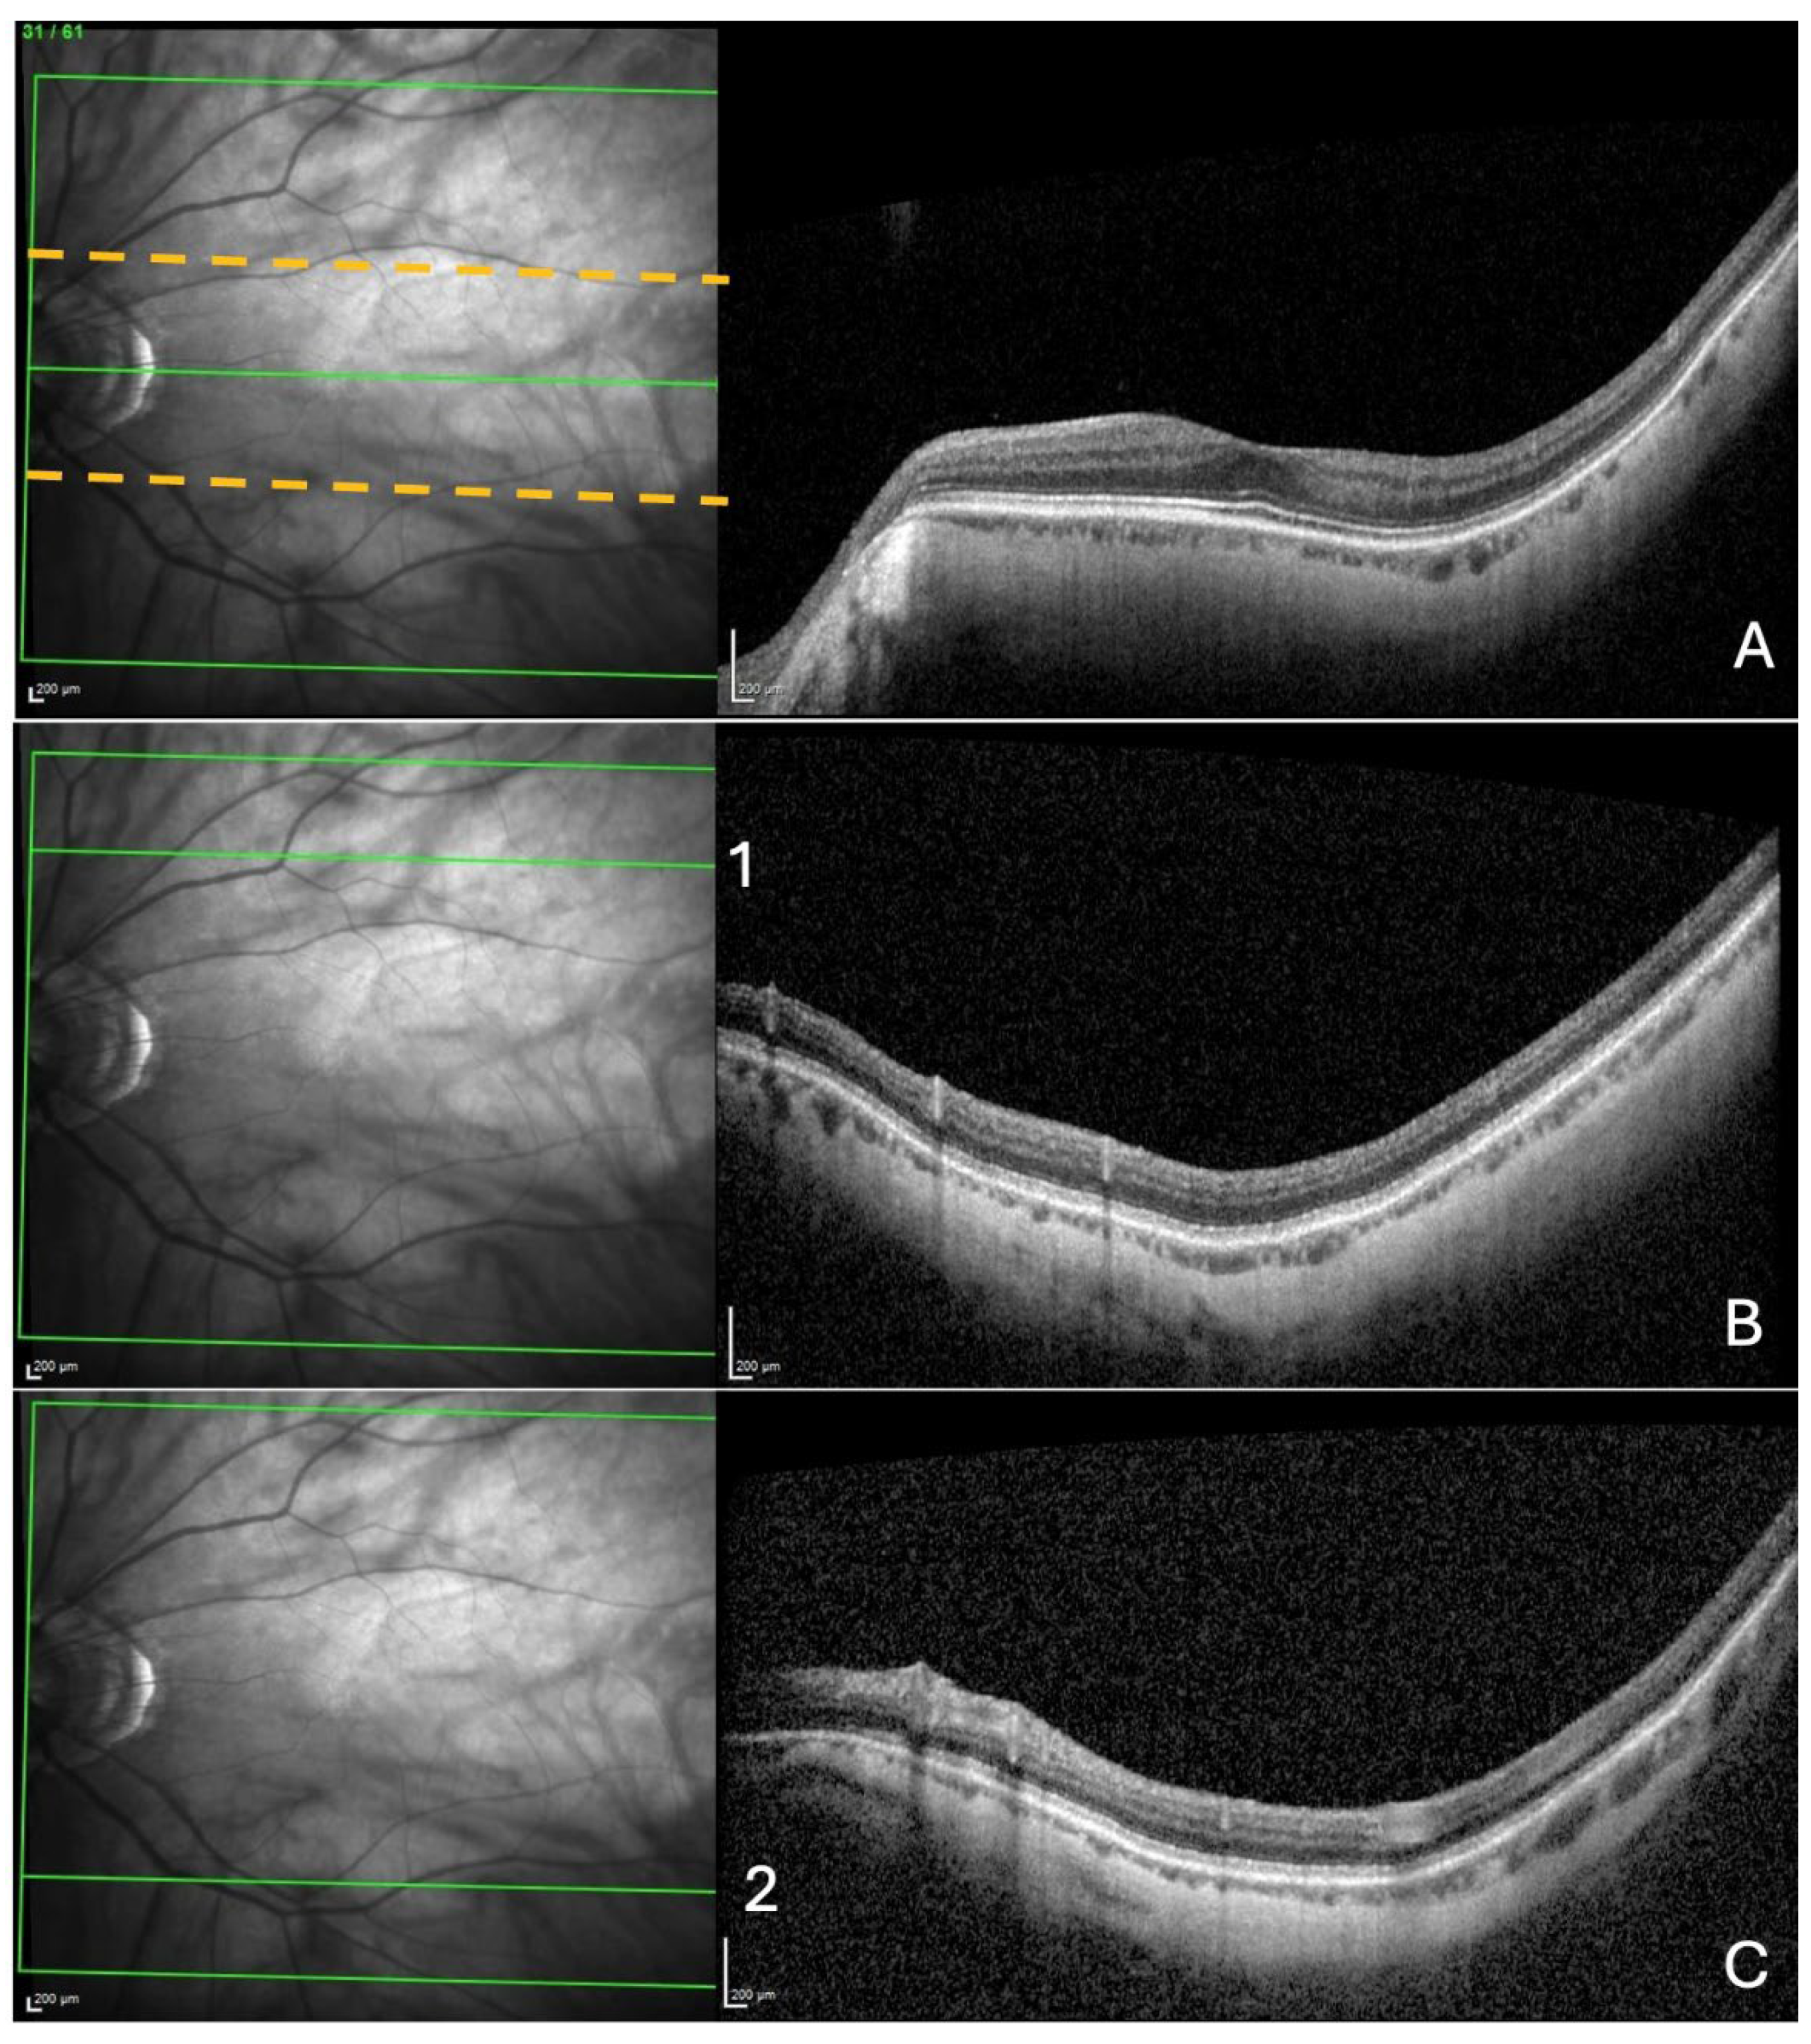

2.1.2. OCT Analysis.

- Search for choroidal thinning in 3 locations in the temporal part of the posterior pole.

- Measurement of the choroidal thinning and distance from fovea to thinning.